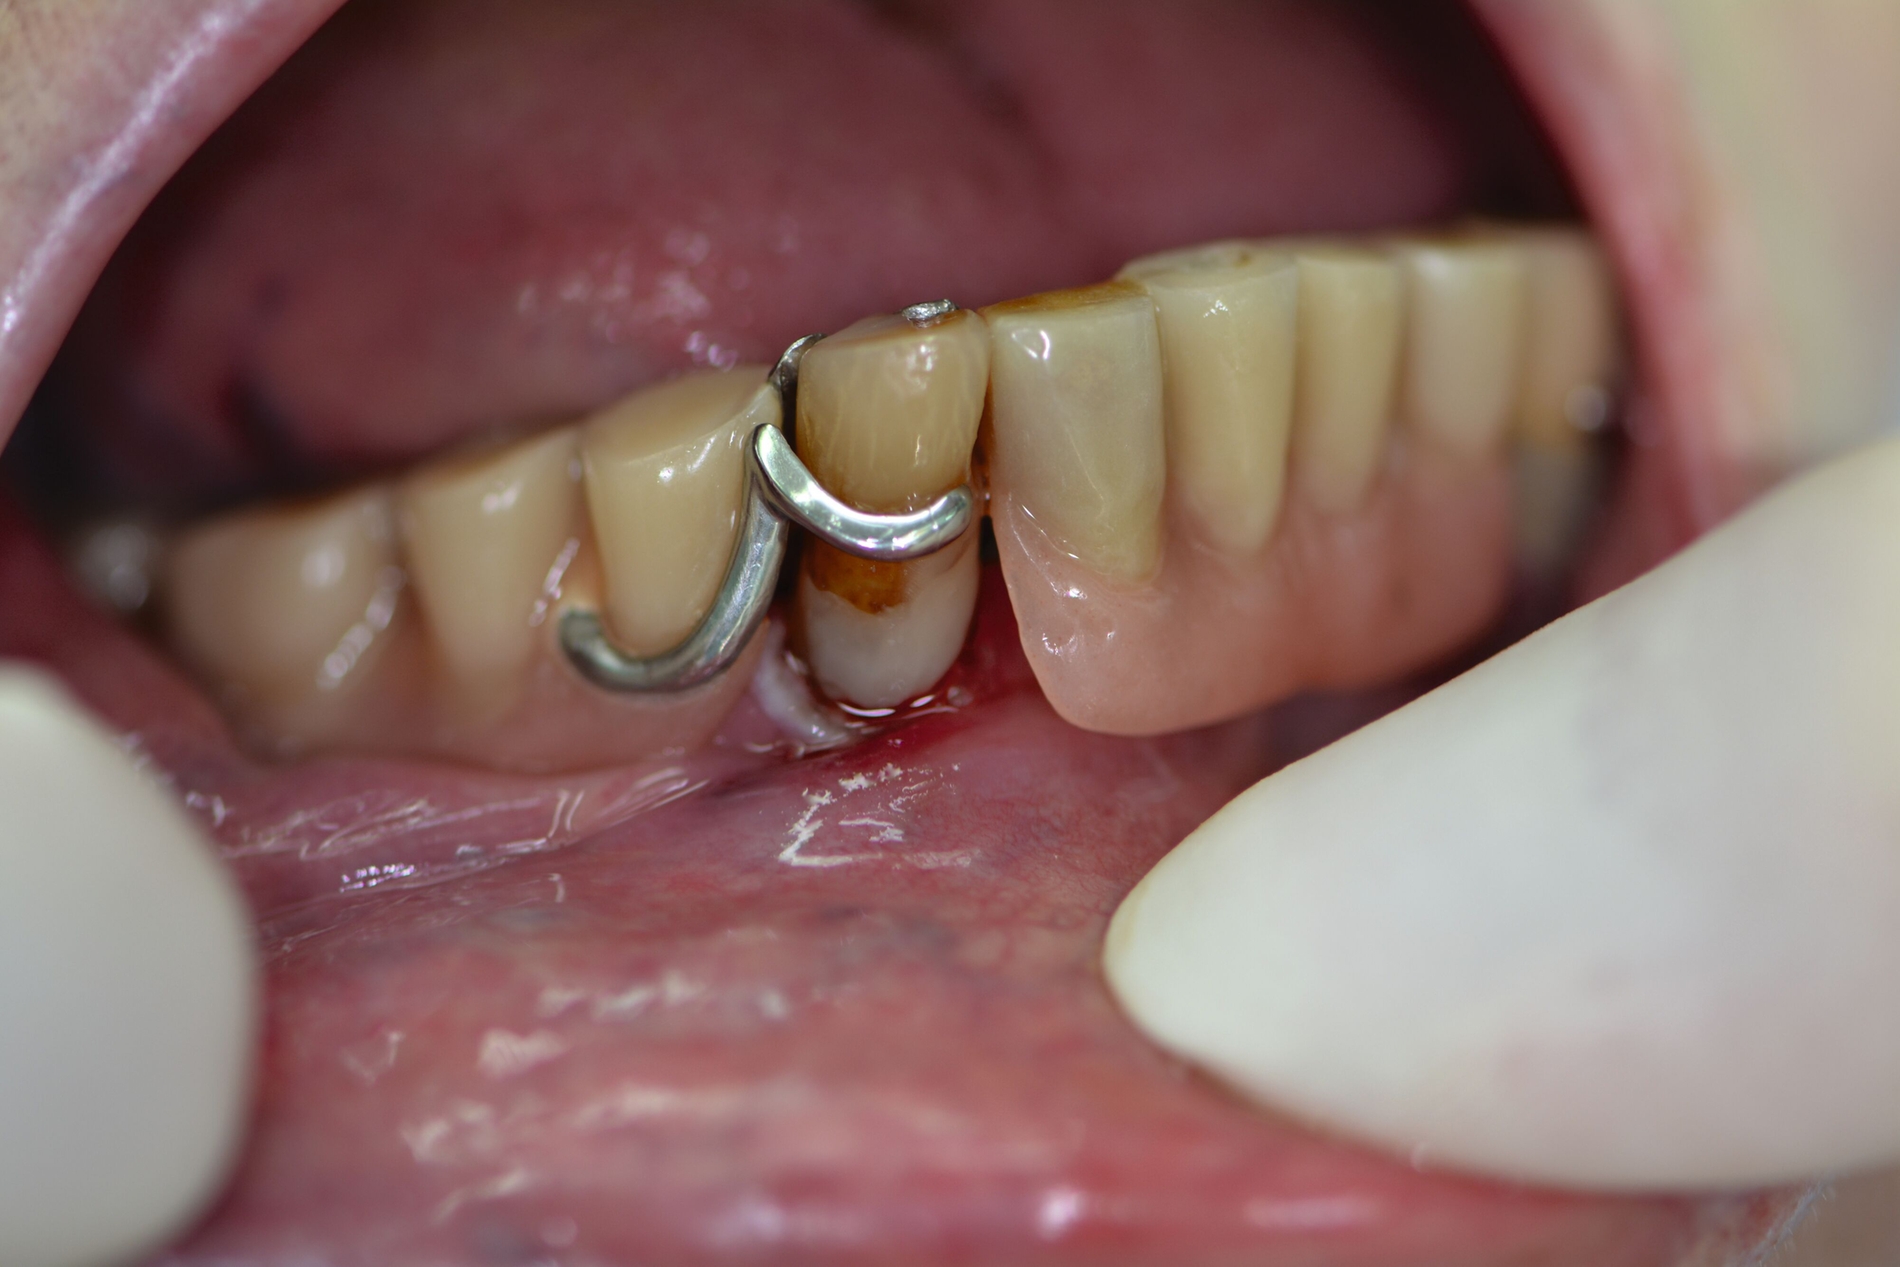

Auch aufseiten der Pflege wurden durch die Einführung des DNQP-Expertenstandards Rahmenbedingungen zur Verbesserung der Mundgesundheit bei Personen mit Pflegebedarf geschaffen. Der Expertenstandard definiert unter anderem das Aufgabenspektrum, den Verantwortungsbereich und das nötige Kompetenzprofil von Pflegefachpersonen in Bezug auf die Mundgesundheit bei Personen mit Pflegebedarf. Als zentrale Anforderung an Pflegefachpersonen formuliert der Expertenstandard zudem die Kompetenz, einschätzen zu können, wann weitere zahnmedizinische Expertise hinzuzuziehen ist [Sirsch et al., 2022]. Um die Maßnahmen zur Förderung der Mundgesundheit nachhaltig zu implementieren, ist ein dauerhafter Austausch zwischen Zahnmedizinern und Pflegeverantwortlichen, unter regelmäßiger Einbeziehung geriatrisch-hausärztlicher Expertise notwendig. Die Telemedizin verspricht in Bezug auf die Verbesserung des Zugangs zu zahnmedizinischen Leistungen für Personen in Pflegeeinrichtungen Zukunftspotenzial [Aquilanti et al., 2020]. Nicht in allen Fällen sind Defizite der Mundhygienefähigkeit absehbar. Nach Unfällen oder Schlaganfällen sind Patientinnen und Patienten eventuell von einem auf den anderen Tag nicht mehr in der Lage, ihre Mundhygiene selbstständig adäquat durchzuführen (Abbildung 4).

Die Hygienefähigkeit des Zahnersatzes spielt eine wichtige Rolle für die Prävention von Mundhöhlen- und Allgemeinerkrankungen. Das regelmäßige Entfernen des oralen Biofilms oder das Ausgliedern von Prothesen vor dem Schlafengehen sind effiziente Maßnahmen, um das Risiko von Lungenentzündungen zu verringern [Chebib et al., 2021]. Pessimistisch müsste man jeden Zahnersatz so planen, dass er beim Verlust der Mundhygienefähigkeit zu einer einfacher pflegbaren Variante umgearbeitet werden kann.